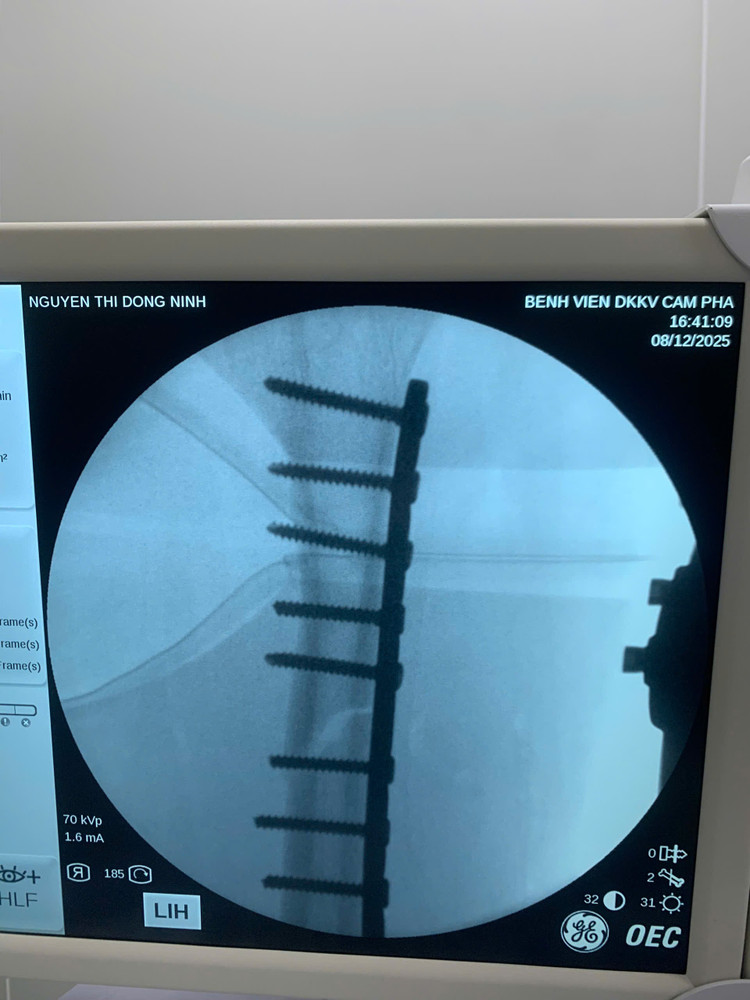

chan-thuong-dui-1.jpg

Hình ảnh kết xương cho bệnh nhân - Ảnh BVCC

Ngày 12/8, ca phẫu thuật được thực hiện bởi ê-kíp gồm: BS. CKI Bùi Trung Hiếu - Phẫu thuật viên chính (Khoa Ngoại); BS.CKII Đỗ Ngọc Lâm - Phó Giám đốc Bệnh viện kiêm Trưởng khoa Phẫu thuật & Gây mê hồi sức, cùng các cộng sự nhiều kinh nghiệm. Ca mổ diễn ra an toàn, không biến chứng.